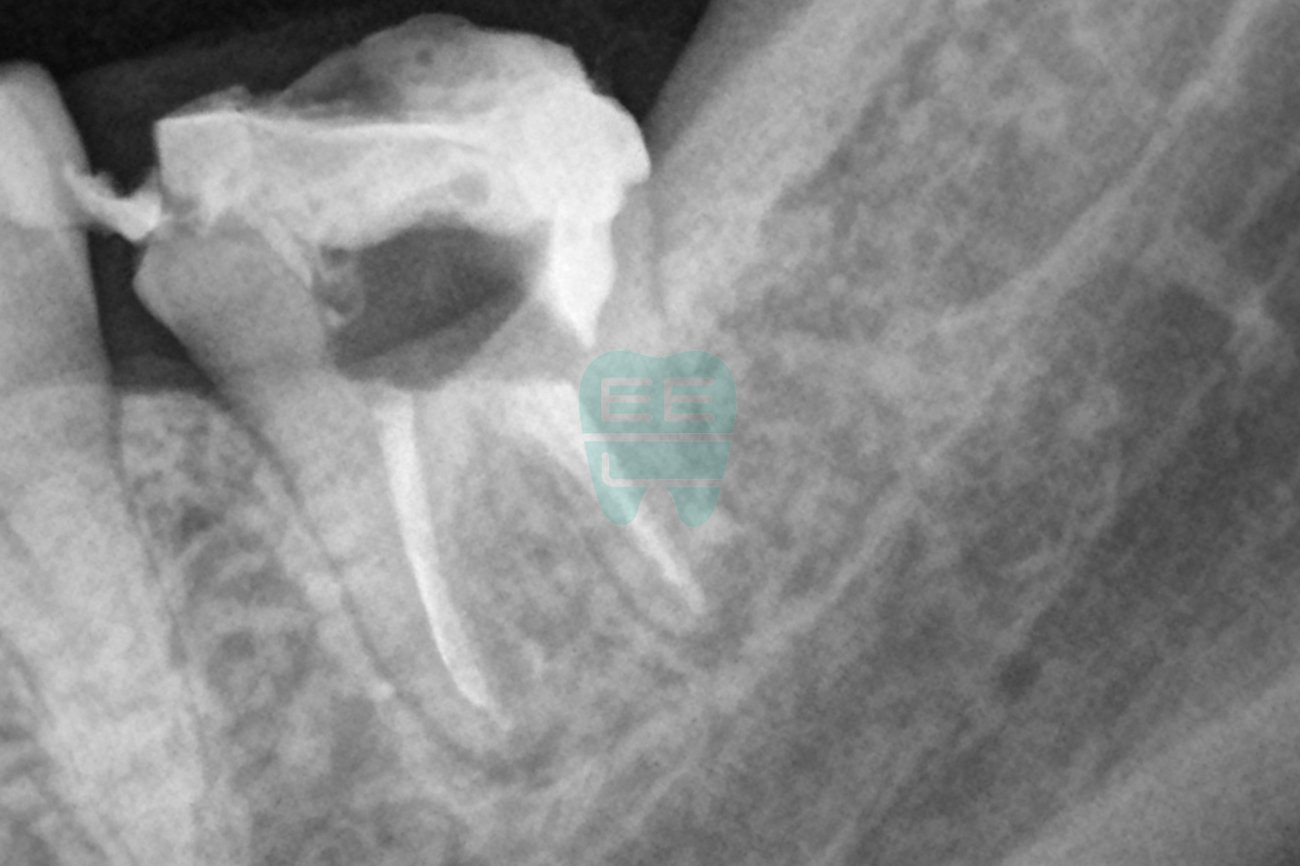

엑스레이 비교 (치료 전 vs 치료 후)

치료 후 엑스레이를 보시면, 기존에 문제가 되었던 부위가 깔끔하게 정리된 것을 확인하실 수 있습니다. 이후 재근관치료를 마무리하고 새로운 크라운을 제작하여 최종 수복을 진행할 예정입니다.